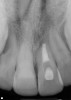

Figure 9  Clinical case of invasive cervical resorption that was deemed nonrestorable and the tooth removed.

Figure 9